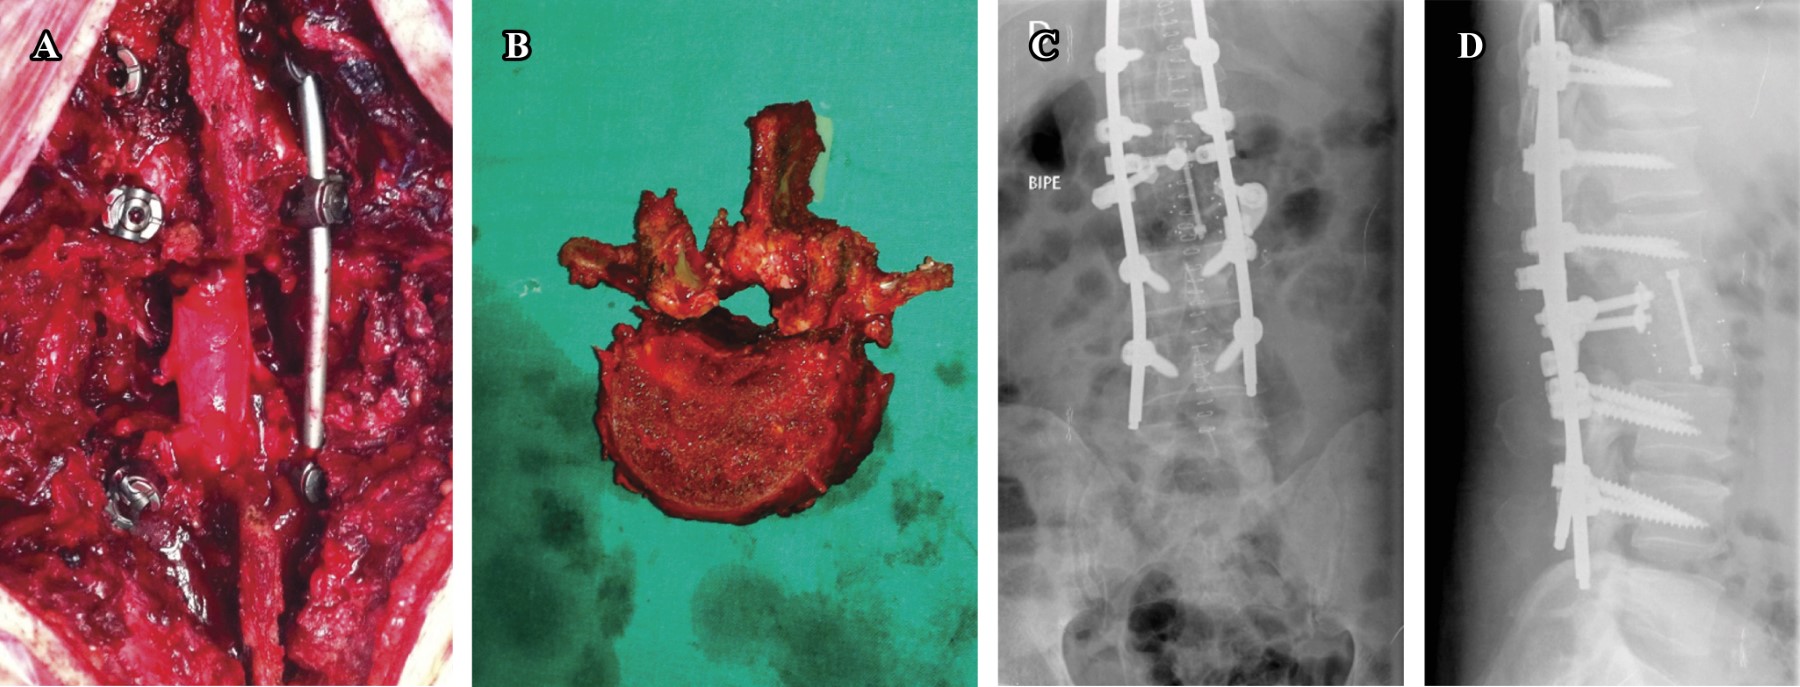

Se intervino la vértebra L2 en un solo tiempo por vía posterior mediante la técnica de Tomita (Figura 4).7 En un segundo procedimiento, que tuvo lugar un mes y medio después de la primera intervención, se resecó parcialmente el arco posterior (base de la apófisis espinosa y espinosa) de T1 (Figura 5). Un mes después de la cirugía se inicia radioterapia dirigida sobre las áreas metastásicas; se realizan 10 sesiones con un campo radioterápico de C7 a T2 y de L1 a L3, con una dosis de 3 Gy/sesión hasta alcanzar una dosis total de 30 Gy.

Figura 4